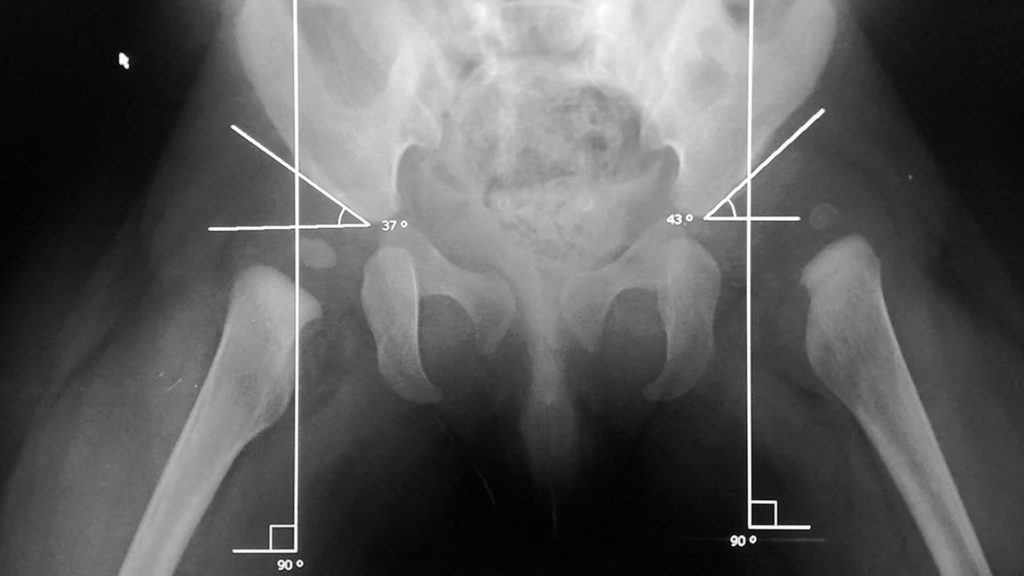

Radiografía especializada en ortopedia infantil